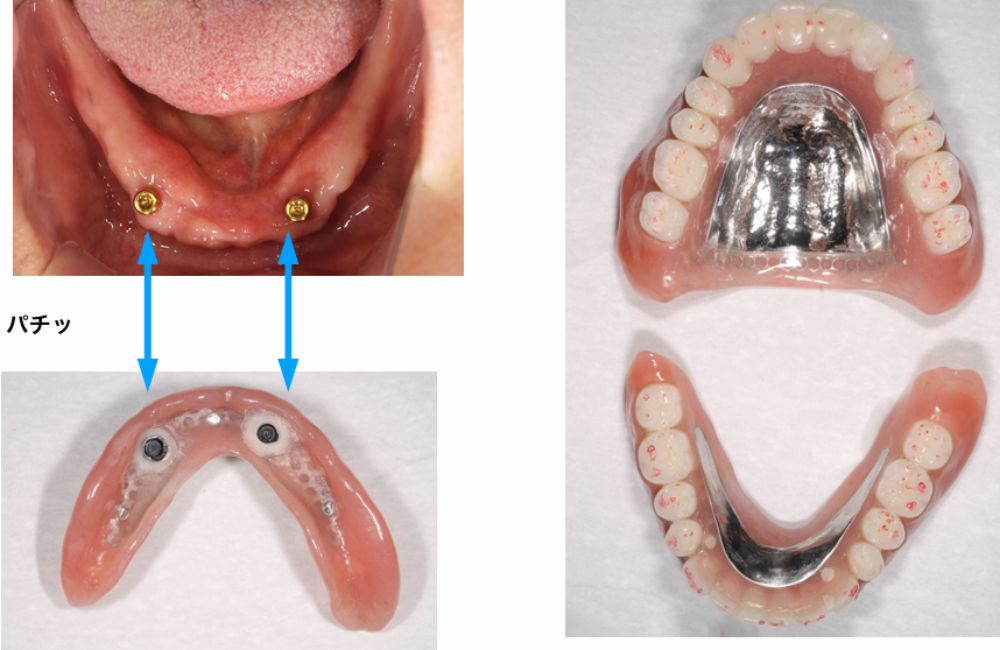

インプラントオーバーデンチャー装着

インプラントオーバーデンチャーの装着前と装着後

インプラントオーバーデンチャーの装着位置と装置